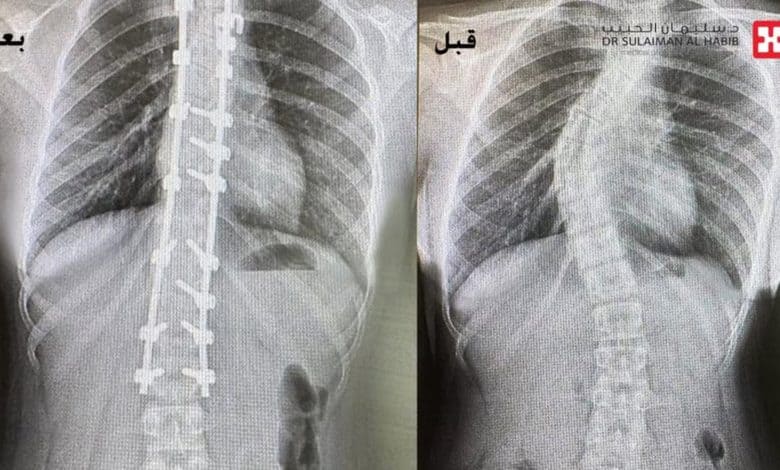

Accordingly, the medical team at Dr. Sulaiman Al Habib Hospital employed state-of-the-art surgical techniques to correct the spinal curvature. This advanced scoliosis surgery also involves precise corrections and the use of modern implants to ensure the spine is realigned properly. This thereby improves the patient’s quality of life significantly.